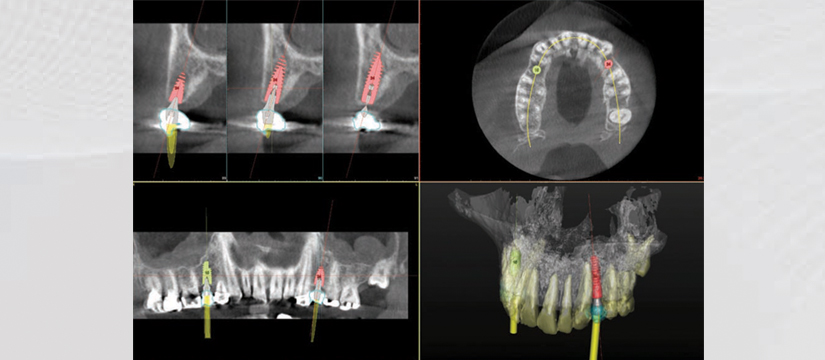

- Panoramic View

- 3D Detntition Positioning